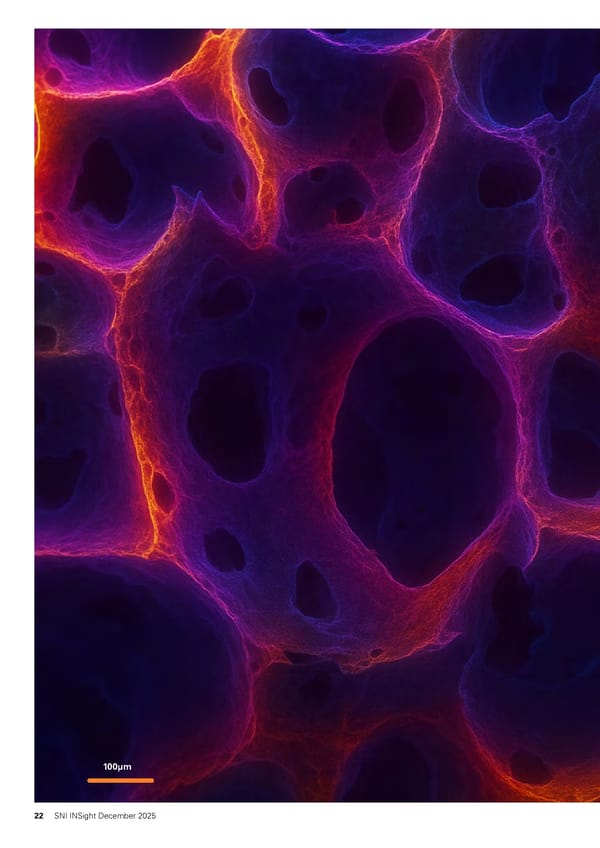

100µm 22 SNI INSight December 2025